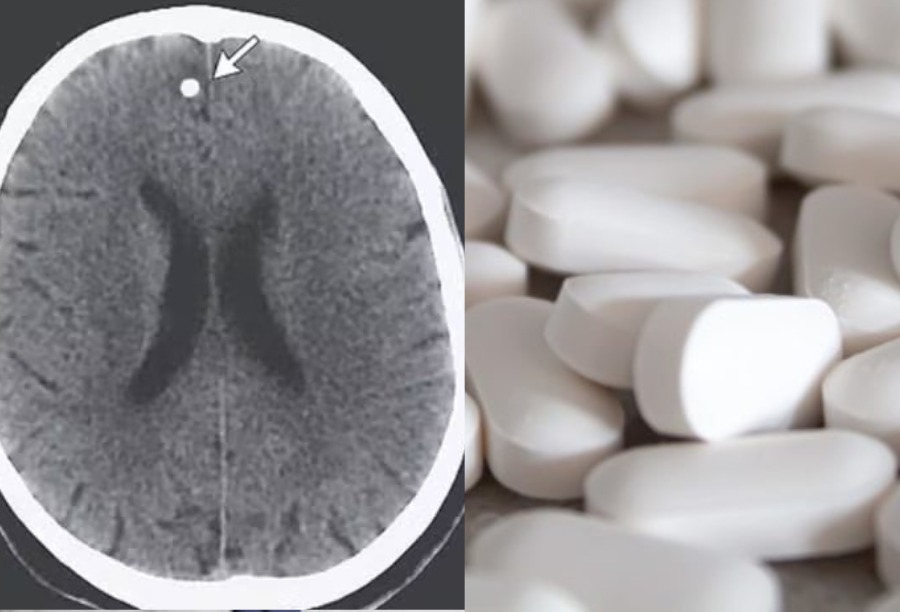

Após idas e vindas ao médico, com pioras de sintomas, manifestação de perda de memória e a prescrição de medicamentos, os quais não apresentaram efeitos, os especialistas decidiram analisar seu cérebro mais de perto e encontraram diversas lesões preocupantes no órgão. Após questionamentos persistentes sobre sua dieta e hábitos, TE confessou aos médicos que consumia ovos de tênia que havia comprados online.

Parasitas em cérebro de mulher. Reprodução.